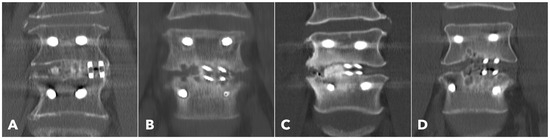

Improved Clinical and Radiological Outcomes with Double-Cage Biportal Endoscopic Transforaminal Lumbar Interbody Fusion: A Comparative CT-Based Study

by Yu-Hao Huang and Jwo-Luen Pao

Diagnostics 2025, 15(20), 2652; https://doi.org/10.3390/diagnostics15202652 - 21 Oct 2025

Cited by 1 | Viewed by 1504

Abstract

Background/Objectives: When transitioning from an older surgical technique to a newer one, we expect improved treatment outcomes and fewer complications. However, direct comparative studies to confirm these advantages are often lacking. Tubular minimally invasive transforaminal lumbar interbody fusion (MISTLIF) has been widely [...] Read more.

Background/Objectives: When transitioning from an older surgical technique to a newer one, we expect improved treatment outcomes and fewer complications. However, direct comparative studies to confirm these advantages are often lacking. Tubular minimally invasive transforaminal lumbar interbody fusion (MISTLIF) has been widely used, but limitations in visualization and endplate preparation may compromise fusion quality. Biportal endoscopic TLIF (BETLIF), a more recent alternative, offers enhanced magnification and superior hemostasis. Still, CT-based comparative data on fusion integrity remain limited. To evaluate the clinical and radiological outcomes following a chronological transition from MISTLIF to BETLIF, using thin-slice CT to assess fusion integrity. Methods: This retrospective study analyzed 179 patients treated by a single surgeon between January 2018 and May 2021. The first 90 cases underwent MISTLIF, followed by 89 BETLIF procedures. Clinical outcomes included Visual Analog Scale (VAS), Oswestry Disability Index (ODI), and Japanese Orthopedic Association (JOA) scores. Radiological assessments at one year postoperatively (X-ray and thin-slice CT) included disc height, segmental lordosis, Bridwell fusion grade, cage subsidence, and subchondral osteolysis. Results: BETLIF was associated with significantly shorter hospital stays (5.7 vs. 7.4 days) and fewer transfusions (0% vs. 14.7%). BETLIF showed significantly better ODI (12.7 vs. 23.5), JOA scores (26.4 vs. 20.6), and comparable VAS improvement. Radiologically, BETLIF had significantly higher fusion rates (93.3% vs. 82.4%), greater disc height restoration, and lower rates of cage subsidence (5.0% vs. 13.7%) and osteolysis (13.3% vs. 52.9%). Conclusions: BETLIF demonstrated superior clinical and radiological outcomes, likely due to enhanced endoscopic visualization and precise endplate preparation. Full article

(This article belongs to the Special Issue Diagnosis and Management of Spinal Diseases)

Show Figures

Figure 1